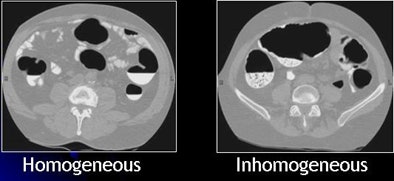

| Inhomogeneous tagging often appears in reduced or nonlaxative CTC. The uneven appearance of tagged materials on CTC data represents a mixture of semisolid fecal materials, air bubbles, fat, undigested foodstuffs, and unevenly distributed contrast agents. |

Inhomogeneous tagging often appears in reduced or nonlaxative CTC data, resulting from a mixture of semisolid fecal materials, air bubbles, fat, undigested foodstuffs, and unevenly distributed contrast agents.